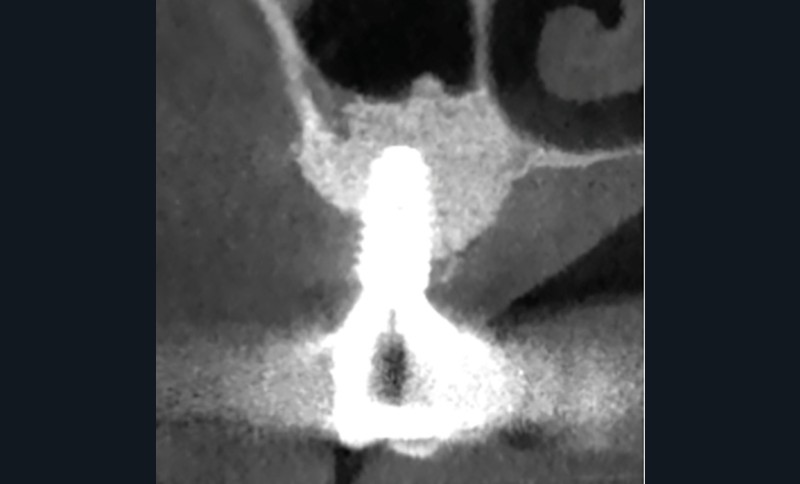

Quatre mois après la suppuration initiale, une fistule est apparue à l’apex de l’implant 16 (fig. 2a). Cette fois, l’examen CBCT a révélé une résorption osseuse considérable (fig. 2b à d). Une chirurgie exploratrice a donc été décidée.